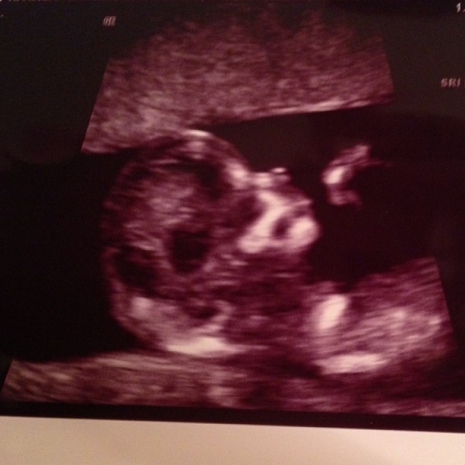

Ultrahangfelvételt mutatott babájáról Danielle Jonas

Kevin Jonas és feleség első gyermeküket várják és a hamarosan anyukává váló Danielle olyannyira lázban ég, hogy a babaholmik után most az első ultrahangos felvételt is közzétette Instagram-profilján. „Nem tudom elhinni, hogy a miénk. Kevinnel áldottnak érezzük magunkat. Nézzétek azt a cuki kis orrocskát” – fűzte a képhez.

Fotó: Instagram